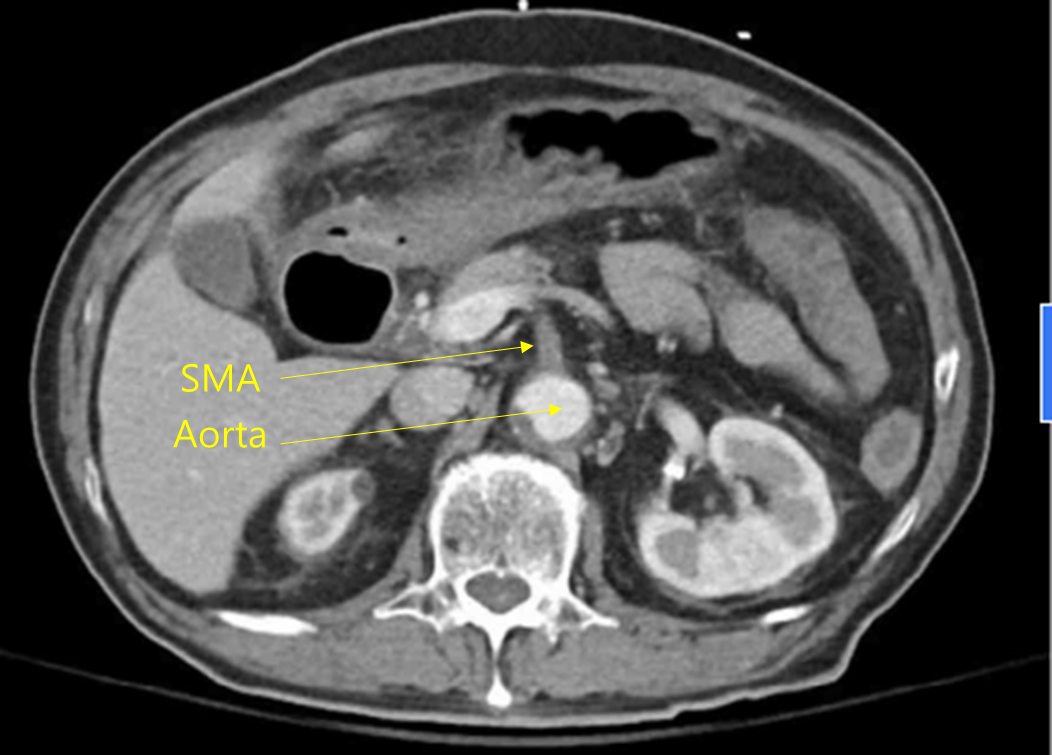

85세 남자가 4시간 전부터 혈변을 본다고 병원에 왔다. 30년 전부터 고혈압, 당뇨병으로 진단받고 약물을 복용 중이다. 식후 갑작스러운 복통이 생겼고 1시간 뒤 점액이 섞인 혈변을 보았다고 한다. 혈압 150/90 mmHg, 맥박 96회/분, 호흡 22회/분, 체온 37.9°C이다. 배는 팽만하고, 배 전체에 압통이 있으나 반동압통은 없다. 복부 컴퓨터단층촬영 사진이다. 진단은?

CT: Ascending colon wall thickening with nearby fluid collection, SMA stenosis/occlusion

고혈압 및 당뇨 기저질환을 가진 고령환자에게서 급성 복통 및 혈변이 발생하였으며, CT상 SMA stenosis/occlusion이 확인되므로 ischemic colitis로 진단한다.

• 혈액검사 결과 leukocytosis 및 CRP/ESR elevation 소견은 환자에게 염증성 병변이 발생했음을 시사하며, 복부 CT상 SMA의 near-total occlusion이 확인되고, SMA가 주된 혈류를 담당하는 ascending colon의 wall thickening과 주변 fluid collection이 허혈대장염이 적절한 진단명일 가능성이 높다.